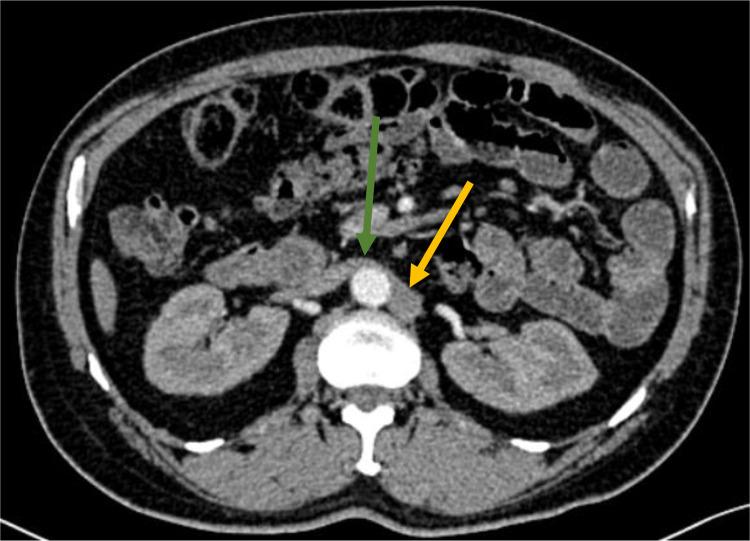

Hemiazygos continuation of a left-sided inferior vena cava (IVC) is an extremely rare developmental anomaly. We present the case of a male patient in whom this condition was incidentally discovered during a thoraco-abdominopelvic CT scan. With the widespread use of contrast-enhanced computed tomography and magnetic resonance angiography, the detection of congenital IVC anomalies has become more accessible. These anomalies are often found incidentally during imaging performed for other clinical reasons. Awareness of this anomaly is crucial before any surgical or endovascular procedures to avoid potential complications.

左侧下腔静脉(IVC)半奇静脉延续是一种极其罕见的发育异常。我们报告一例男性患者,该病症在胸腹部盆腔CT扫描时被偶然发现。随着增强计算机断层扫描和磁共振血管造影的广泛应用,先天性IVC异常的检测变得更加容易。这些异常常在因其他临床原因进行的成像检查中偶然发现。在进行任何外科手术或血管内介入手术之前,认识到这种异常对于避免潜在并发症至关重要。